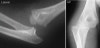

수상 직후 AP, Lat 사진이 필수적이며, 정복 후 재촬영으로 동반된 골절을 확인합니다.

X-ray : 주관절 탈구(Elbow dislocation)